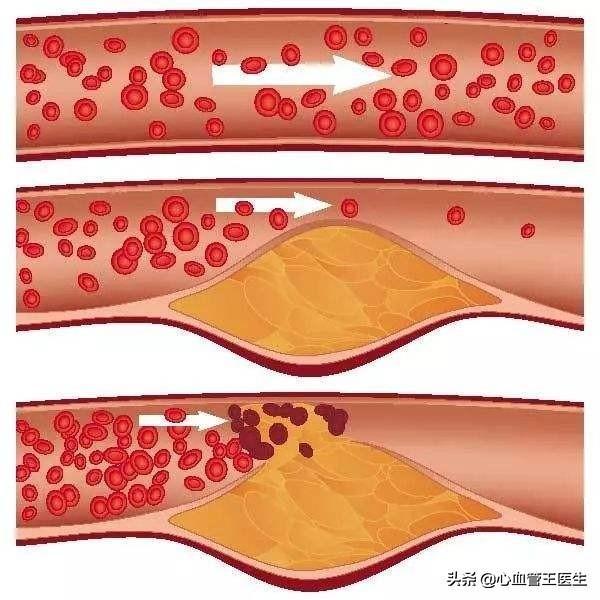

脳梗塞は脳血管障害の一種であり、専門的には「虚血性脳卒中」と呼ばれる。脳血栓症以外にも心房細動などの原因もあります。簡単に言えば、脳梗塞にはいろいろな原因があるが、その中で最も多いのが脳血栓症である。そして、このような脳血栓症の脳梗塞はアテローム性動脈硬化病変、すなわち病理学的基盤がアテローム性プラークに基づくものである。

そして、アテローム性動脈硬化プラークは一般的な慢性病変であり、その発生と発症は高血圧、糖尿病、高脂血症などの多くの要因に影響される。長期にわたる高血圧、高血糖、高脂血症を管理しないと、人体各部の動脈に動脈硬化性プラークが発生しやすくなり、この動脈硬化性プラークが脳動脈に発生すると、脳血栓症発生の下地を作ることになる。たとえば、時間の経過とともに、血圧、血糖、血中脂質がまだコントロールされていない、アテローム性プラークがますます大きくなり、ますます不安定になり、この時、アテローム性プラークが大きくなりすぎたり、突然破裂したりすると、その場で血栓症が発生し、動脈血管が閉塞し、脳梗塞も発生する。

人体を例にとって言えば、水道管の老化は動脈硬化のようなもので、動脈硬化がプラークを生成するのは「さび色の斑点」、「汚れ」のようなものだ。

違いは、プラークが破裂して血栓症を促進する可能性があることで、これが心血管疾患の急性発作の原因である。

実際、血栓症は防御機構である:

例えば、皮膚が破れて出血した場合、出血は自動的に止まるが、これは血栓症の結果である。 血栓が形成され、破れを塞ぐことで出血が止まるのである。しかし、この破断は血管のプラーク上で起こり、破断した場所から自ら修復して血栓が形成されるが、血管局所では限られたスペースしかないため、血管の局所的な狭窄、あるいは閉塞を引き起こす。